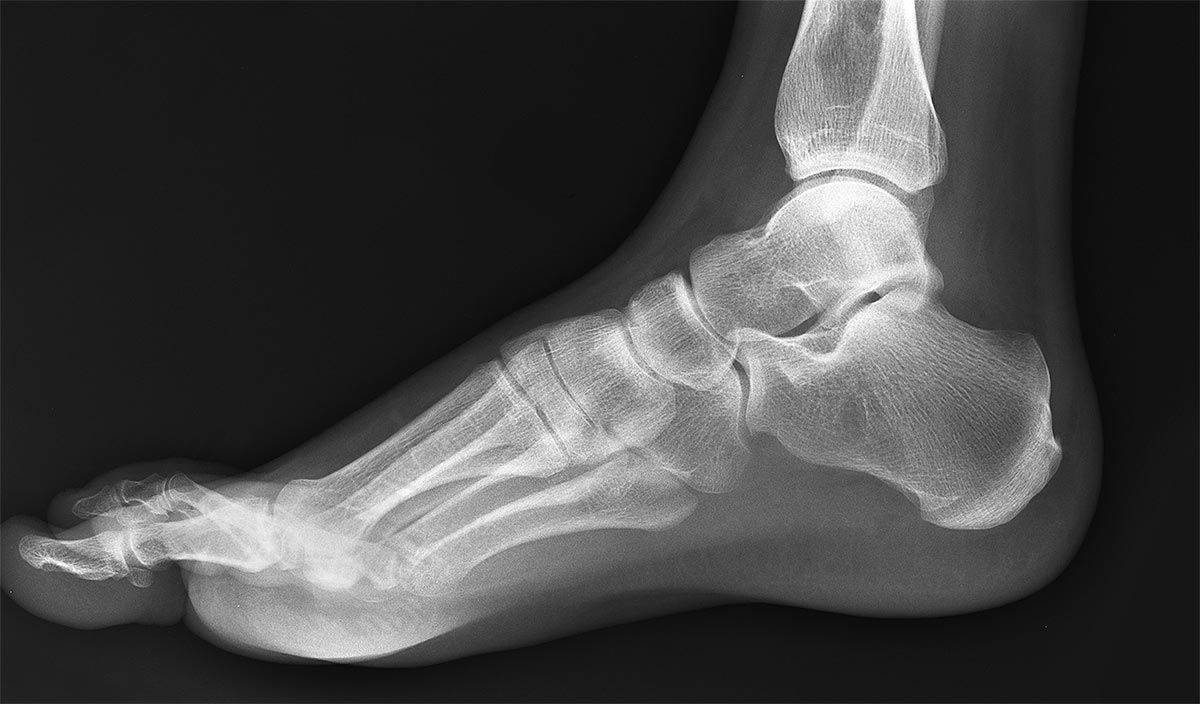

Рентген снимки делаются в стоячем положении, когда нагрузка на стопы максимальна, в поперечном ракурсе и продольном. На снимках четко видно есть заболевание или нет. Так же необходима компьютерная томография сустава подтаранного и описание отклонений первого пальца и плюсны (часть стопы под пальцами). При положительном результате врач определяет разновидность плоскостопия и его степень.

Молодые люди с «непризывной» степенью плоскостопия обязательно отправляются медкомиссией на дополнительное обследование. Основным методом его проведения является рентгенография. Обычно снимки делают в двух проекциях под нагрузкой. Затем по ним измеряется угол продольного свода стопы. У здорового человека его значение не превышает 130 градусов. При плоскостопии первой степени он составляет 131-140 градусов, второй – 141-155 градусов, третьей – более 155 градусов. С этим показателем связано несколько нюансов, которые нередко определяют «окончательную» категорию годности призывника:

Исследование состояния стоп проводят при максимальной нагрузке в положении стоя, а также в продольном и поперечном ракурсе. Полученные изображения позволяют четко определить наличие отклонений в состоянии стоп или их отсутствие.

Существуют такие виды плоскостопия как продольное, поперечное и комбинированное. Продольное определяется на основании снимка стоп в боковой проекции. Поперечное определяется на основании снимка стоп в прямой проекции. Комбинированное сочетает в себе продольное и поперечное. После проведения рентгеновского исследования стоп врач-рентгенолог расчерчивает рентгеновский снимок. На основании расчерченного рентгеновского снимка врач-рентгенолог измеряет высоту свода стопы и измеряет угол Белера, затем определяется точная степень заболевания.На рентгенограммах путем построения треугольника определяется угол продольного свода и высота свода. При прохождении медицинской комиссии следует озвучить жалобы врачу-хирургу и представить медицинские документы, в которых указано о наличии выраженной степени плоскостопия. Врач должен направить молодого человека на дополнительное медицинское обследование по акту от военкомата. Точную степень заболевания определяют по рентгенографии стоп под нагрузкой в прямой и боковой проекциях.